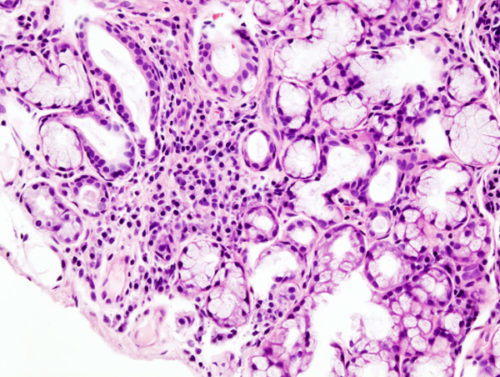

On ne connaît pas exactement la cause de ce syndrome, c’est pourquoi la pose d’un diagnostic est souvent longue et difficile car d’autres maladies présentent les mêmes symptômes. Il faut prendre en compte la présence de symptômes buccaux et oculaires et la présence d’auto-anticorps. Il peut même être nécessaire d’effectuer une biopsie d’une glande salivaire.